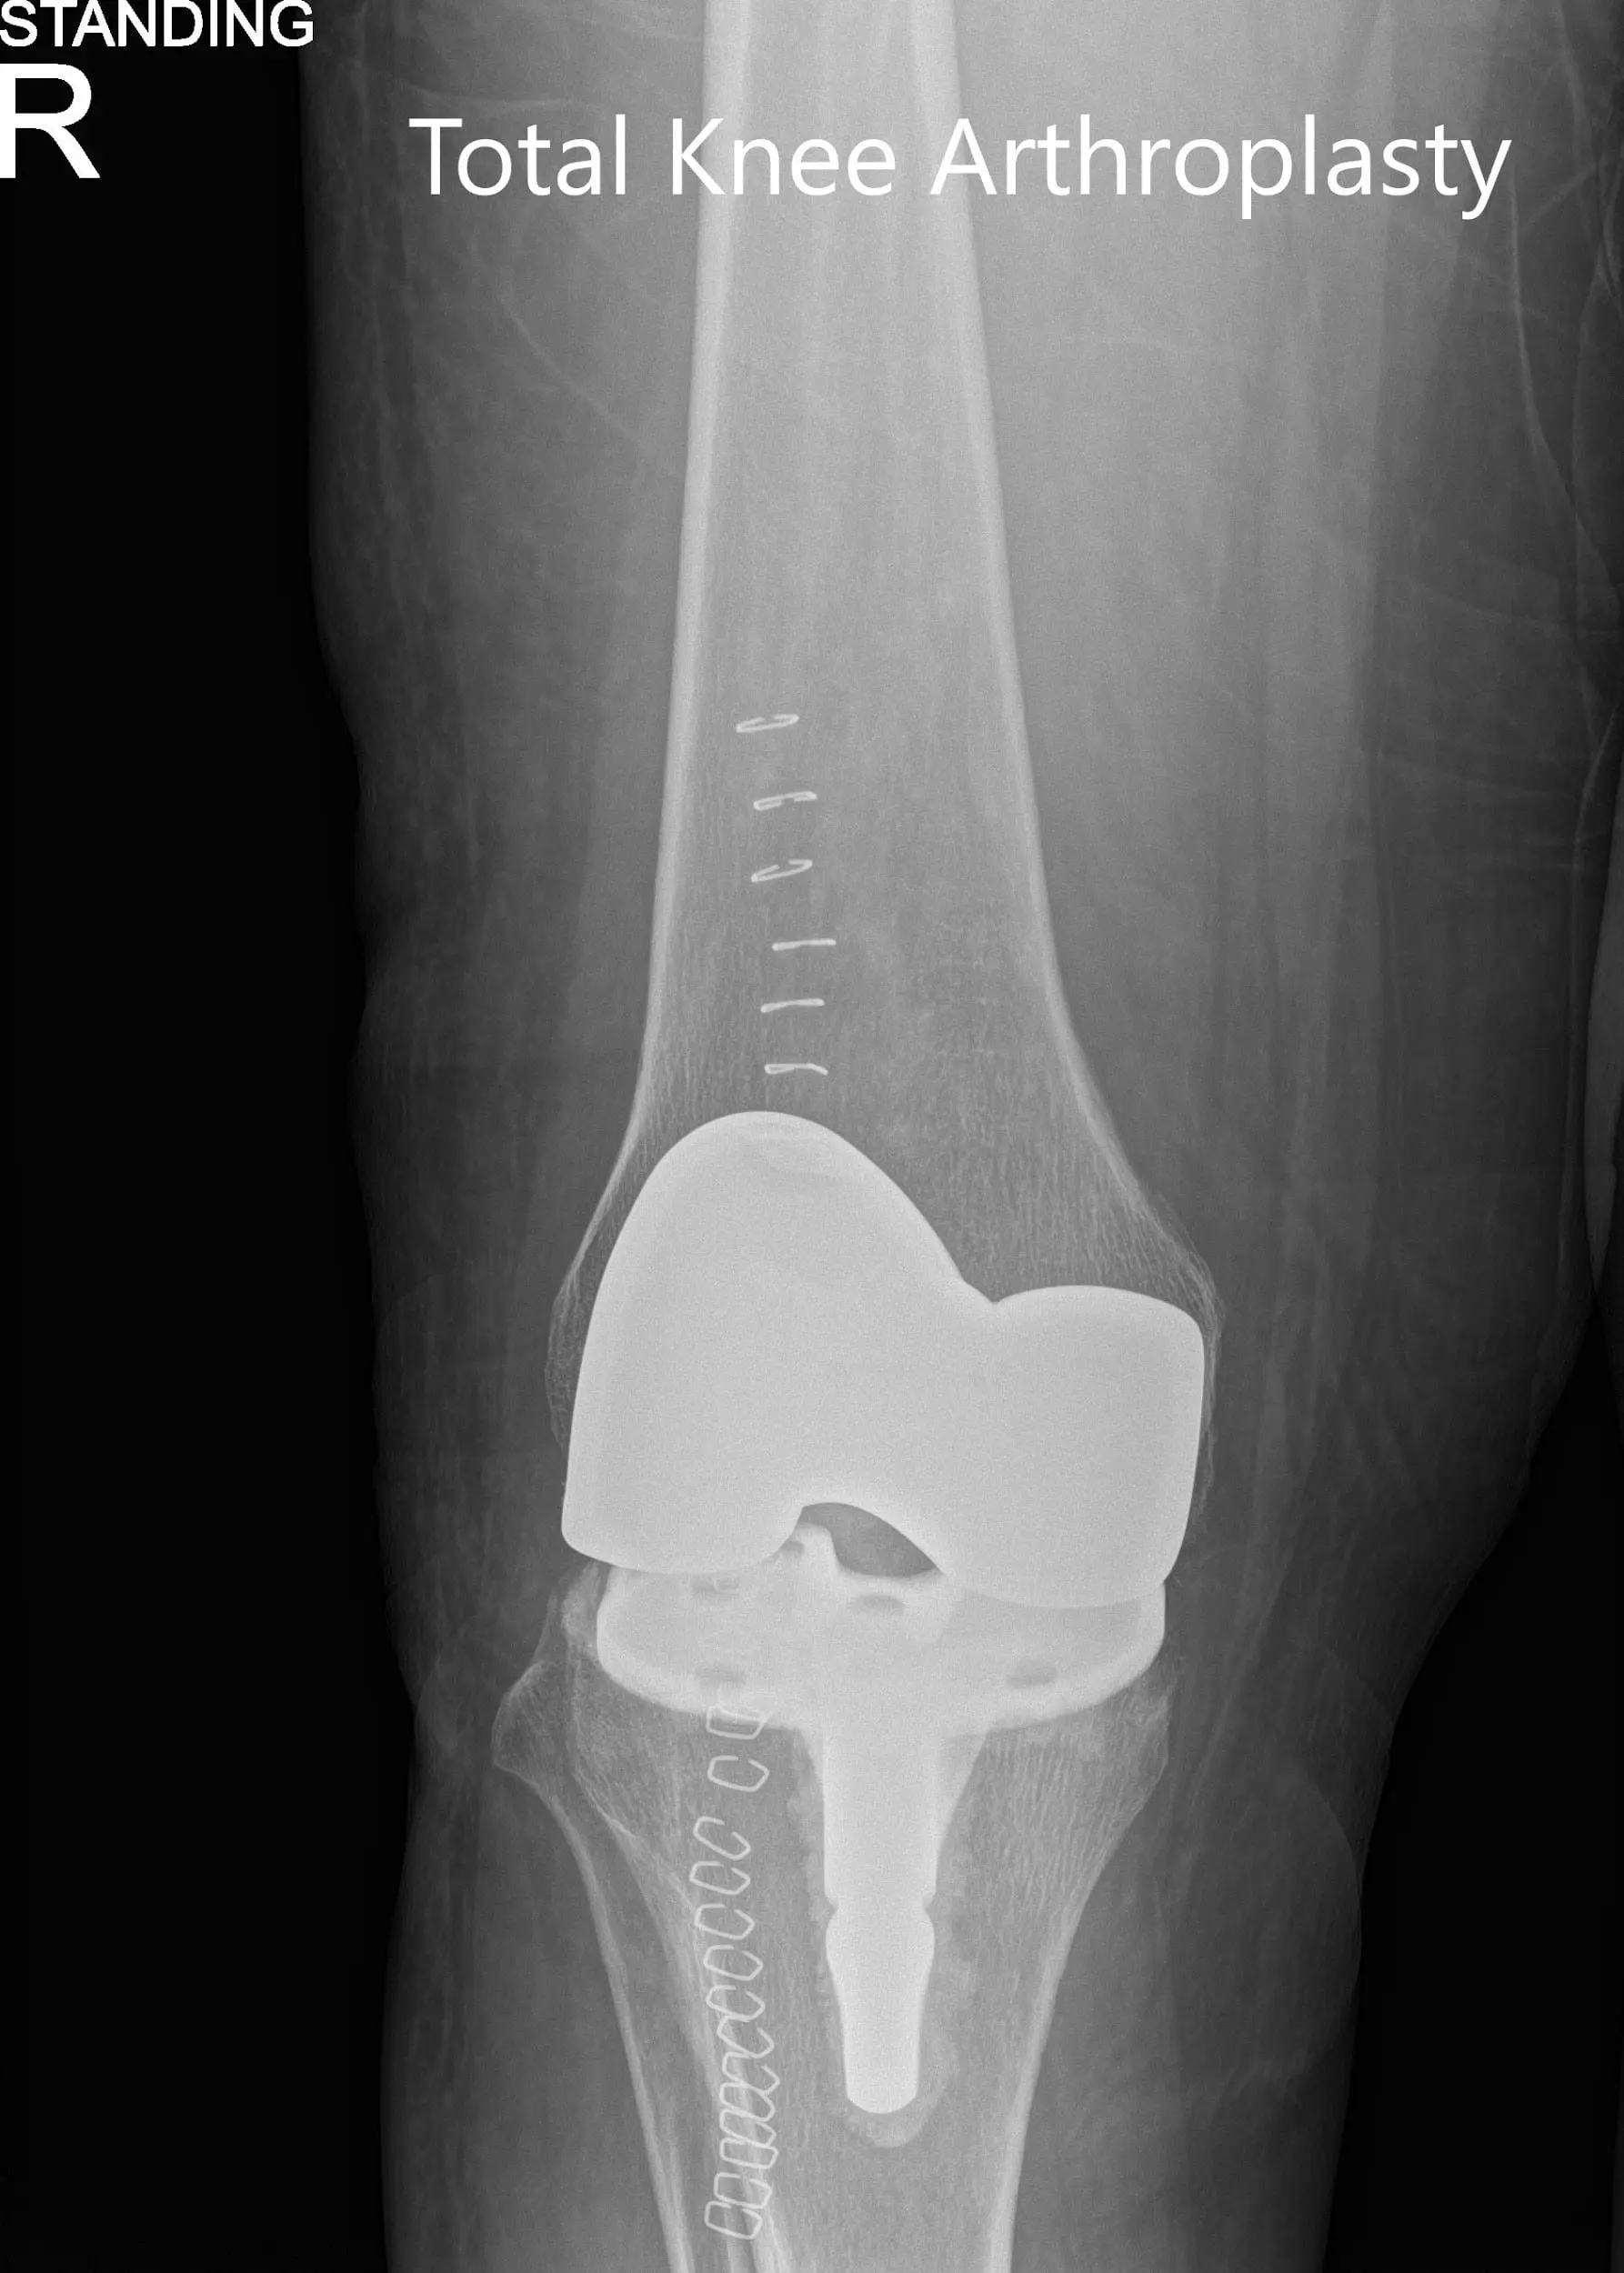

Postoperative x-ray showing the anteroposterior and lateral views of the right knee

Postoperative x-ray showing the anteroposterior and lateral views of the right knee - img 2

Postoperative x-ray showing the anteroposterior and lateral views of the right knee.